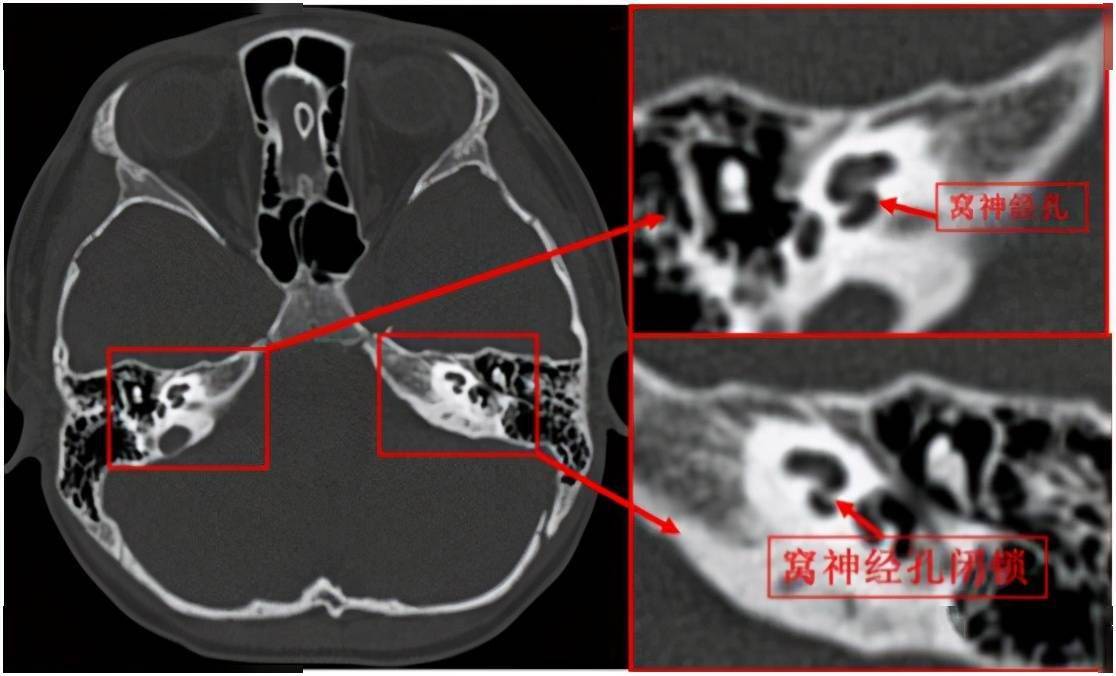

仔细查看扬扬的磁共振及ct影像,发现左侧蜗神经孔闭锁,蜗神经缺如

仔细查看扬扬的磁共振及 ct 影像,发现左侧蜗神经孔闭锁,蜗神经缺如